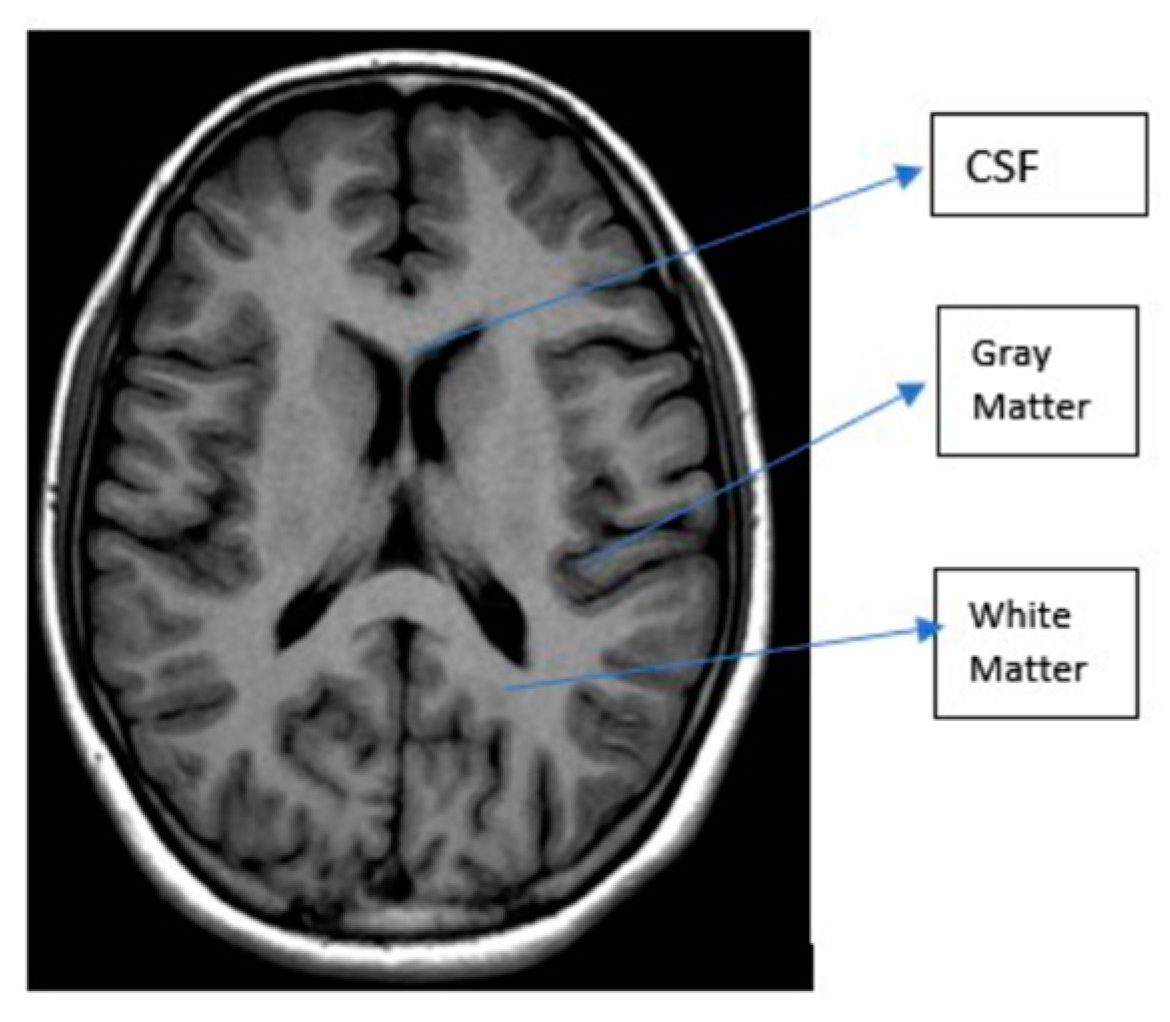

3.1. MRI

| T1 | T2 | Flair | |

|---|---|---|---|

| White Matter | Bright | Dark | Dark |

| Grey Matter | Grey | Dark | Dark |

| CSF | Dark | Bright | Dark |

| Tumor | Dark | Bright | Bright |